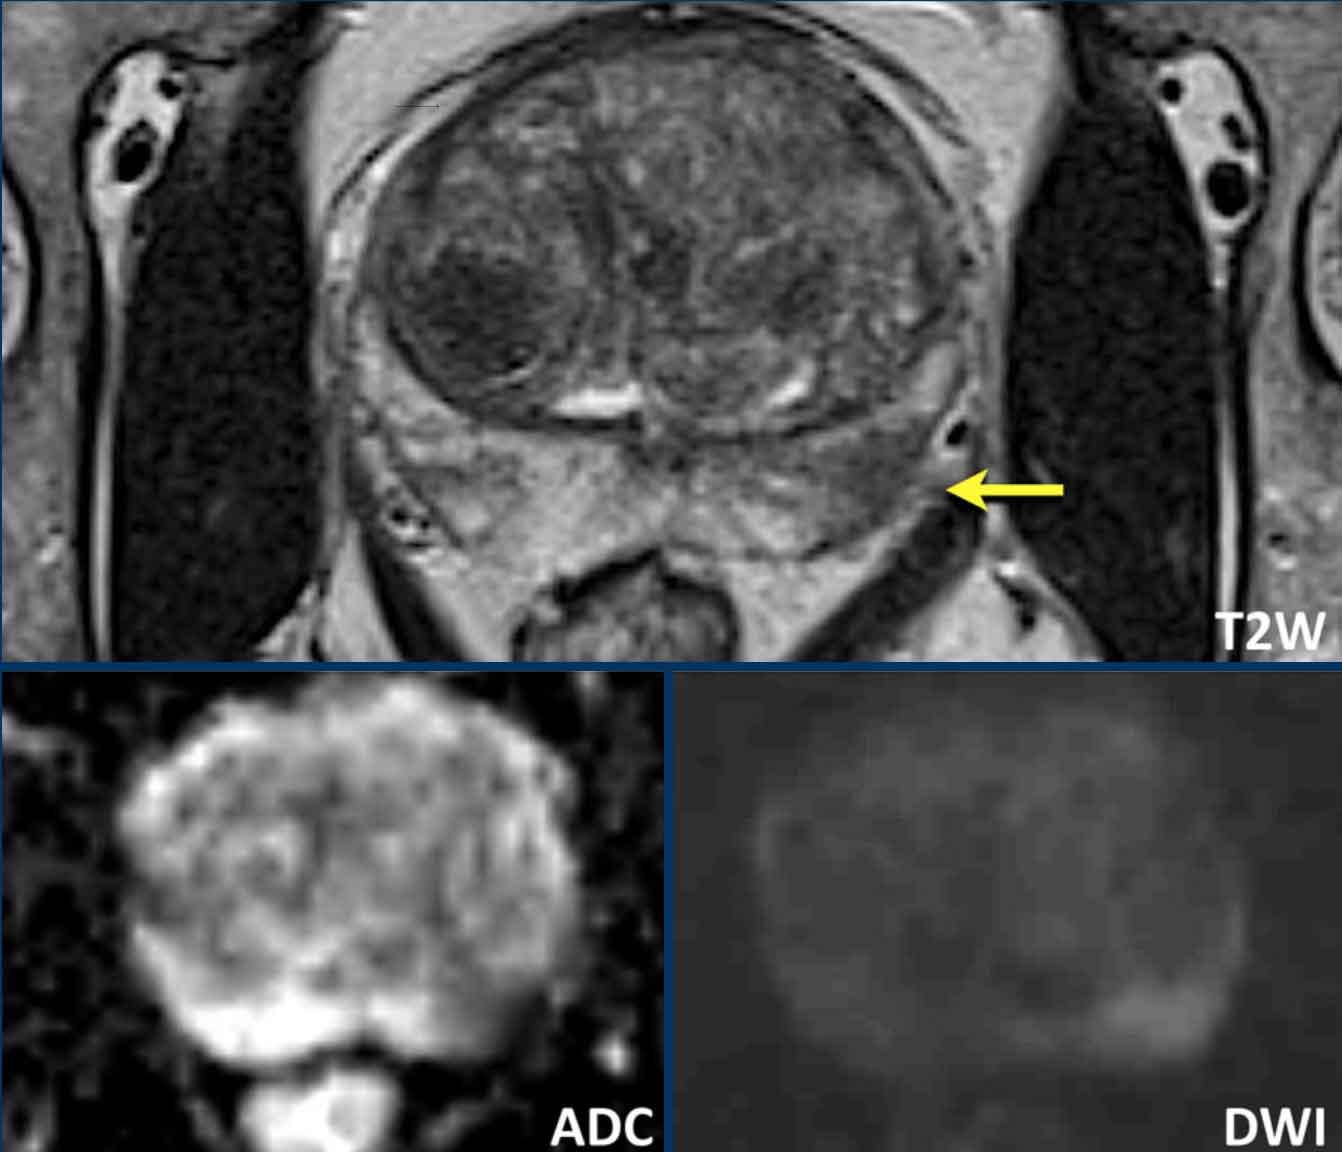

Ung thư tuyến tiền liệt tại vùng ngoại vi (PZ)

Đối với vùng ngoại vi, chuỗi xung DWI/ADC là chuỗi xung chính để xác định phân loại đánh giá PI-RADS.

Hãy quan sát hình ảnh trước và mô tả những gì bạn thấy.

Một tổn thương kích thước 16 mm (không hiển thị phép đo) được phát hiện, nằm ở phía sau vùng ngoại vi của phần giữa tuyến tiền liệt bên phải.

Tổn thương này được xếp vào phân loại PI-RADS 5, dựa trên giảm tín hiệu rõ rệt trên ADC và tăng tín hiệu rõ rệt trên DWI (điểm 5 – chuỗi xung chính), đối chiếu với giảm tín hiệu rõ rệt trên chuỗi xung T2W (điểm 5).

Điểm Gleason là 3+4, cho thấy nguy cơ trung bình của một ung thư có tính xâm lấn cao.

Tổn thương không tiếp xúc với vỏ bao giả và không có dấu hiệu xâm lấn ra ngoài tuyến tiền liệt.

Các tổn thương nghi ngờ tại vùng ngoại vi thường có các đặc điểm sau trên chuỗi xung T2W:

- Bờ không rõ

- Giảm tín hiệu trên ADC và chuỗi xung T2W

Các đặc điểm ít nghi ngờ hơn trên chuỗi xung T2W bao gồm:

- Hai bên

- Đối xứng

- Thay đổi tín hiệu phân bố lan tỏa

- Hình nêm

- Ổ giảm tín hiệu có bờ rõ